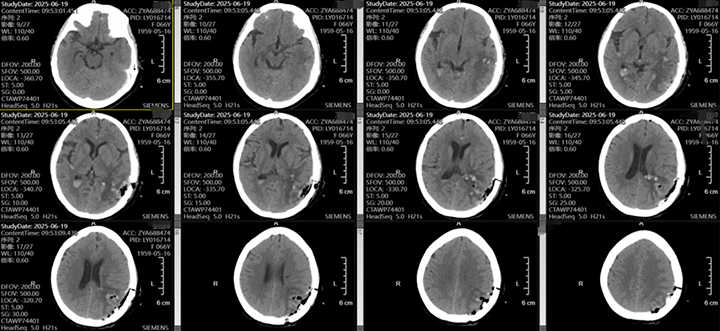

随着老龄化的加剧,脑出血的患者越来越多,不同部位的脑出血,可能因不同的原因导致,该患者左侧颞枕叶脑出血,吴全主任考虑脑血管畸形可能较高,但患者意识渐昏迷,先行血肿清除,但骨窗主要位于后枕顶部,若是去除骨瓣,不利于术后脑组织的保护,且后期需要颅骨修补,故与患者家属充分沟通后,予以骨瓣回纳,术后治疗上加强脱水,帮助患者渡过脑水肿关,患者术后第一天意识即转清楚。后期待病情平稳后在行DSA检查评估,明确此次出血是否为脑血管畸形、动脉瘤等原因导致的出血。